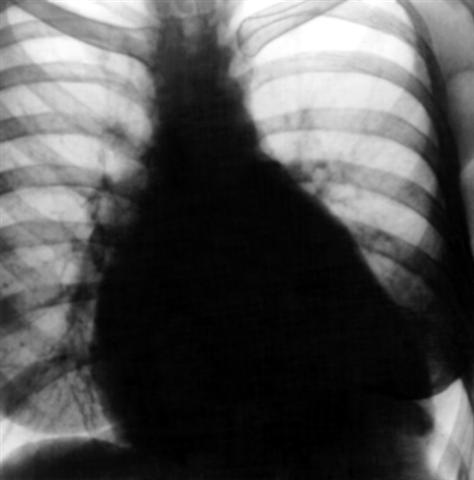

Рис. 22. Рентгенограмма грудной клетки больного с сочетанным митральным пороком в комбинации с трикуспидальной недостаточностью: выбухание третьей дуги и пульмонального конуса, расширение поперечника тени сердца, в том числе значительно вправо.